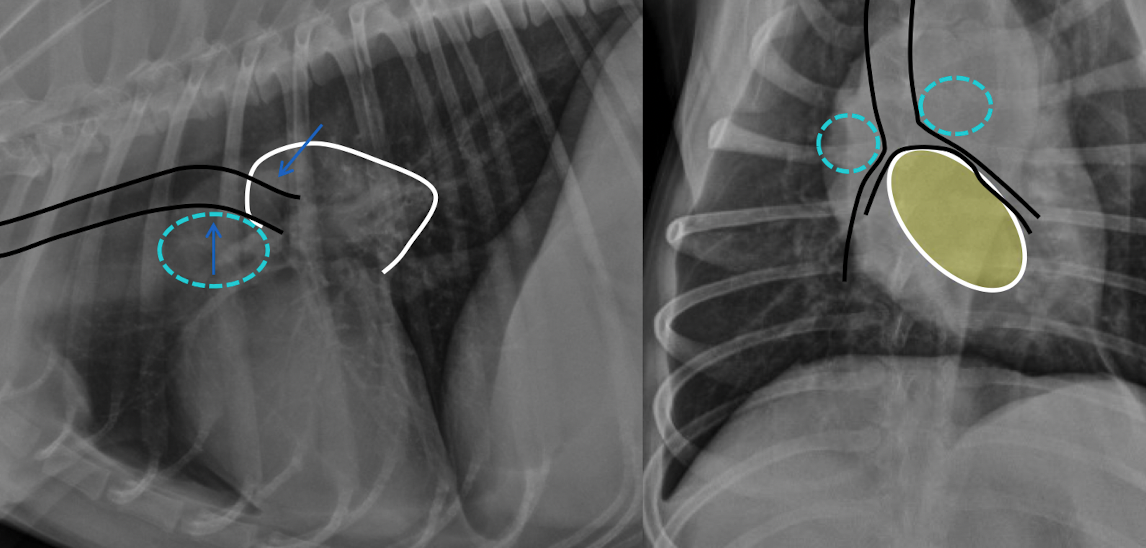

24

where are the lymph nodes

mediastinal lymphadenopathy

middle tracheobronchial cause ventral deflection, L and R cause dorsal deflection

widening of mediastinum

where are lymphnodes in this pt with medistinal lymphadenopathy